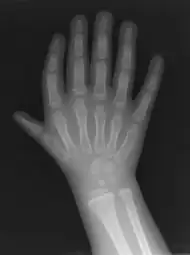

Triphalangeal thumb (TPT) is a congenital malformation where the thumb has three phalanges instead of two. The extra phalangeal bone can vary in size from that of a small pebble to a size comparable to the phalanges in non-thumb digits. The true incidence of the condition is unknown, but is estimated at 1:25,000 live births.[1] In about two-thirds of the patients with triphalangeal thumbs, there is a hereditary component.[2] Besides the three phalanges, there can also be other malformations. It was first described by Columbi in 1559.[3]

The diagnosis can be made on a physical examination and on an X-ray.[4]